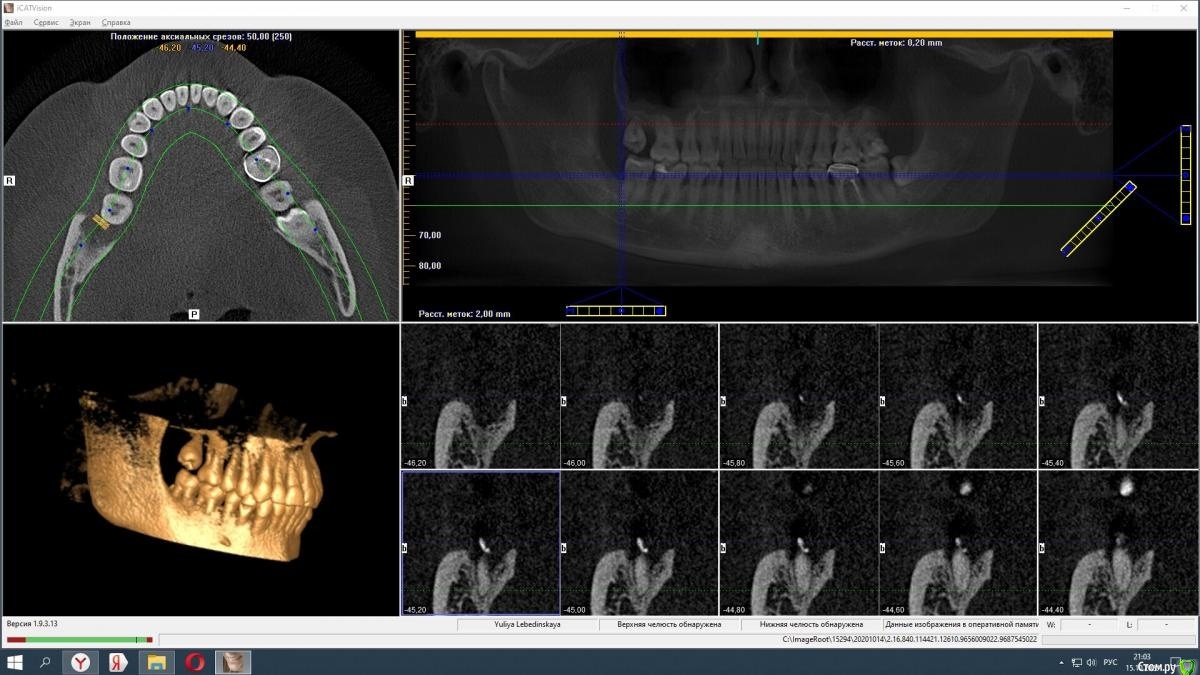

Спилка Опубликовано 15 октября, 2020 Автор Поделиться Опубликовано 15 октября, 2020 Загрузите кт на файлообменникhttps://yadi.sk/d/cU-dxQlKtbsNfQКЛКТ И фото места где был зуб Ссылка на комментарий

Irouil Опубликовано 16 октября, 2020 Поделиться Опубликовано 16 октября, 2020 Вот именно мнение клиницистов меня и интересует, насколько правильно меня лечилиИменно это сказать клиницист не может в принципе, такие заключения даются на экспертизе врачом-экспертомКакой результат по вашему достигнут в стационаре, не подохла?Я бы выразился иначе, но суть Вы передали верно: главная цель лечения пациентов в экстренной медицине (а инфекционные воспалительные процессы, в первую очередь флегмоны, в челюстно-лицевой области являются показанием именно для применения такого вида лечения) - спасение жизни, ибо угроза для нее была. Теперь по существу Во-первых я не вижу на предоставленной компьютерной томограмме потенциально инфицированных фрагментов, угрожающих Вашему здоровью. И расскажите подробнее про губу - отмечается ее онемение? Сможете обрисовать карандашом область онемения и сделать фото? Ссылка на комментарий

Zlata-doctor Опубликовано 17 октября, 2020 Поделиться Опубликовано 17 октября, 2020 (изменено) Я не вижу никаких осколков на представленных снимках. Замечу, даже если бы они там и были, это не может являться причиной флегмоны. Патофизиология данного процесса гораздо более сложна и связана также с особенностями флоры вашей полости рта, вашего иммунитета, с непростой анатомией данной области, сложностью удаления и другими факторами. И таки да, околочелюстной области как анатомического образования, не существует. Промывание, введение лексредств и дренирование проводятся врачом по показаниям, он не должен 100% это сделать, а иногда это и нежелательно. Также хочу Вам сказать, что здесь собрались врачи, которые абсолютно бесплатно в рамках своей компетенции пытаются помогать вам, пациентам. И никакая это не цеховая солидарность, просто проводить экспертизу и ставить вердикт на расстоянии, не имея полной задокументированной истории вашей болезни-непрофессионально, преступно и аморально. К сожалению, люди сейчас воспитаны на скандальных ТВ роликах, где диагнозы обвинения, а заодно и приговор раздаются на раз-два. Здесь такого горлопанства в погоне за сенсацией не будет. Мы вам очень сочувствуем и желаем скорейшего выздоровления. Изменено 17 октября, 2020 пользователем Zlata-doctor 5 Ссылка на комментарий